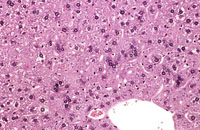

Adult mouse liver with scattered multinucleated hepatocytes

A mouse treated chronically with chlordane, showing enlarged hepatocytes with multiple nuclei.

Multinucleated hepatocytes in a B6C3F1 male mouse.